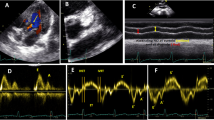

New Zealand rabbits received cholesterol (1%) or normal chow for 1 month. At 30 days, superoxide anion levels, assessed by ESR spectroscopy, NAD(P)H oxidase (NOX) activity, and dihydroethidium (DHE) staining of aortas were higher in the cholesterol-fed (CF) group compared with control (respectively, 4.0 ± 0.6 Arbitrary Units/mg (AU/mg) vs. 2.6 ± 0.3, p < 0.05; 4231 ± 433 vs. 2931 ± 373 AU/mg, p < 0.05; 21.4 ± 1.2 vs. 12.9 ± 1.7% fluorescence/mm2, p < 0.001). NOX gp91phox and p67phox expression in the aortas were higher in the CF group vs. control (1.5 ± 0.2 vs. 0.5 ± 0.2, p < 0.001; 0.9 ± 0.2 vs. 0.3 ± 0.2, p < 0.05). The endothelium-dependent relaxation evaluated on the iliac arteries was higher in control than in the CF group (64.8 ± 10.1 vs. 13.1 ± 3.70%, p < 0.001). The cardiac diastolic pressure estimated on isolated hearts was higher in the CF group than in control (21.1 ± 4.1 vs. 10.3 ± 1.4 mmHg, p < 0.05) after 60 min of ischemia.